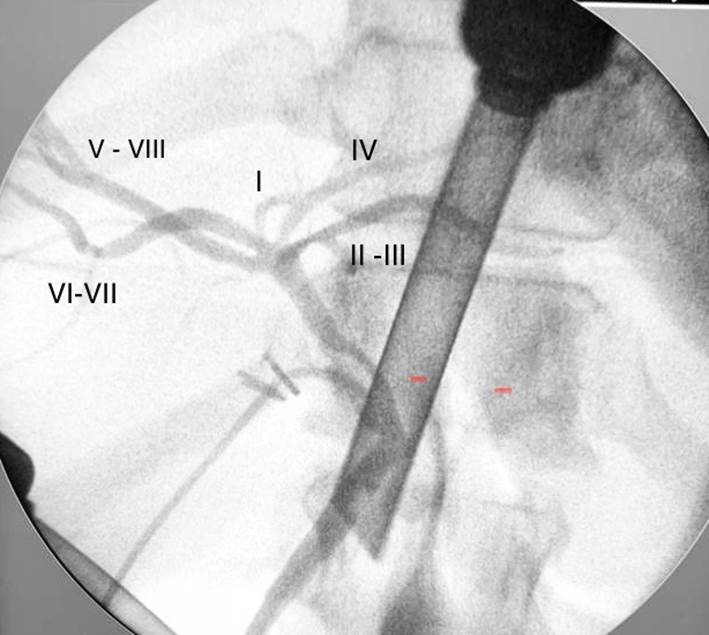

La anatomía biliar es modal (normal) entre el 53-58 % de la población1 . La anomalía más frecuente se vincula con el abocamiento del conducto lateral posterior derecho en el hepático entre el 11%-15,6 %. 1-2 . Más allá de ello, se conocen múltiples variaciones, bien estudiadas y clasificadas por diversos autores, producto de la compleja embriología hepato-bilio-pancreática . Entre ellas, la denominada confluencia escalonada ("convergence étagée","selved confluence"), que admite muy diversos patrones de hilio hepático biliar 3. En menos de un 5% de los casos se puede observar la llegada por separado de todos los canalículos segmentarios independientes para formar un hilio sin “hepáticos”(Fig.1), como en la imagen hallada en el curso de una colangiografia intraoperatoria (Fig. 2), realizada durante una colecistectomía de urgencia.

Fig. 2 Se muestra en esta colangiografía intraoperatoria, realizada a través de un conducto cístico largo de implantación normal, el hilio biliar formado por la confluencia independiente de los conductos segmentarias hepáticos. La imagen no permite definir si el conducto del segmento I, termina en el sector más proximal del común del VI-VII o directamente en la confluencia. El hepático izquierdo, esta sustituido por la terminación independiente del II-III y el IV.